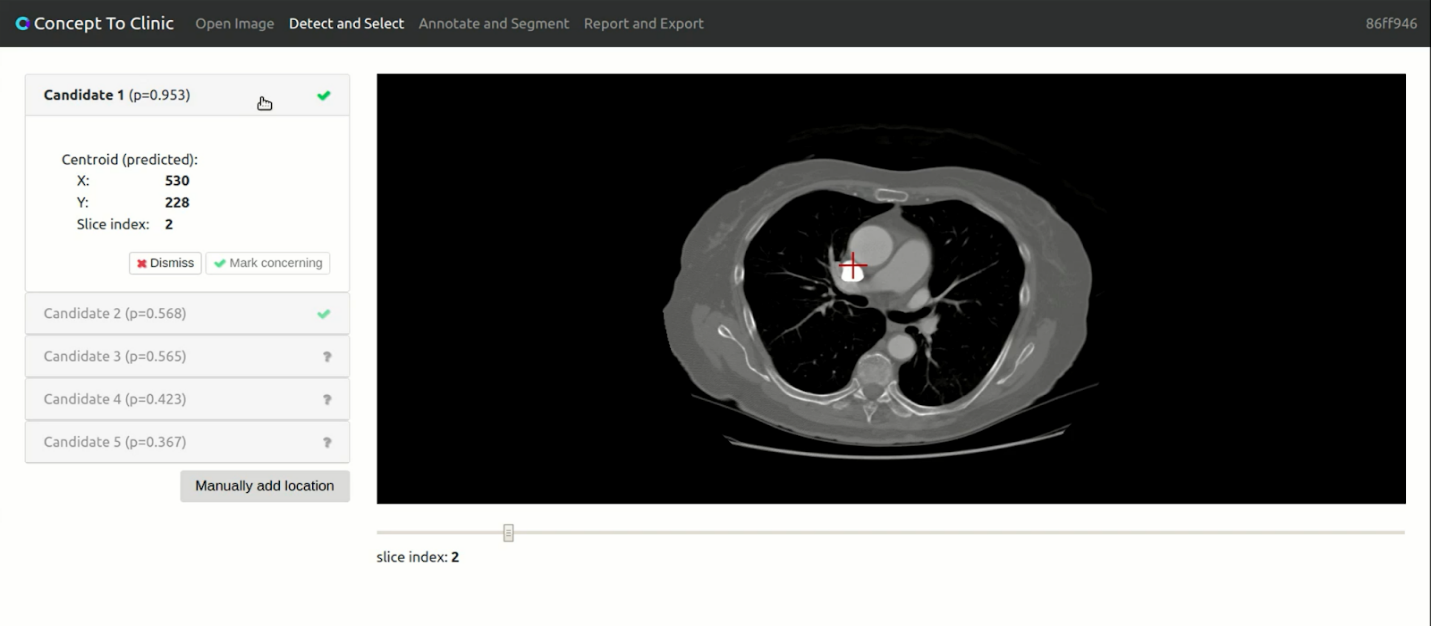

Last year, DrivenData ran a data science challenge with the Addario Lung Cancer Foundation focused on building an open source software application for lung cancer detection. The $100,000 Concept to Clinic event aimed to bridge the artificial intelligence (AI) application gap and to make AI advances useful not just for data scientists interested in cutting-edge technology, but for clinicians on the front lines of lung cancer detection, and the patients they serve. More than 600 developers signed up to partake in the challenge, and transformed a sketch to a prototype in seven months.

Figure 2: The application above is one of the open source projects DrivenData maintains for the data science, machine learning, and software development communities.